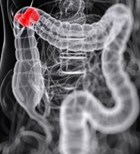

גידולים במעי הגס ניתנים להסרה ע"י טיפול כירורגי בגישה...